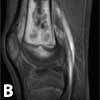

An MRI scan with gadolinium was ordered for further evaluation of the vague knee pain. It was performed using a 1.5-T magnet.

The MRI scan of the right knee revealed extensive marrow infiltration with multiple pockets of fluid in the distal femoral diaphysis and metaphysis measuring 7.4 3 1.5 3 1.5 cm. High signal was demonstrated on both T2-weighted fat-saturated and T1-weighted fat-saturated post-gadolinium sequences involving the medullary cavity and the surrounding cortex and periosteum (Figure 2). No subperiosteal fluid collection or fistulas were evident.